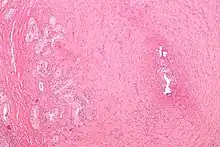

Micrograph of vasitis nodosa (left of image). H&E stain. | |

Vasitis nodosa is a complication experienced in approximately 66% of men who undergo vasectomy.[1] It is a benign nodular thickening of the vas deferens, in which small offshoots proliferate, infiltrating surrounding tissue.[2] It can be mistaken for low-grade adenocarcinoma by pathologists,[3] and is implicated in late vasectomy failure.[2]